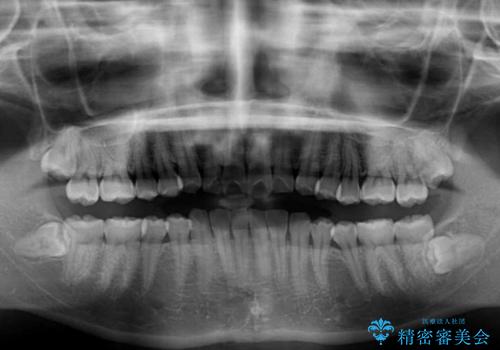

- 上の前歯が出っ張っている気がするとのことで来院された患者様です。

急いで治す必要性がないとのことで、自分のペースでのんびりと治療を行えるインビザラインにて矯正治療を行うこととしました。

半年もせずにインビザラインを全く使用することができなくなってしまったので、治療開始から1年ほどでワイヤー矯正へ変更することとなりました。